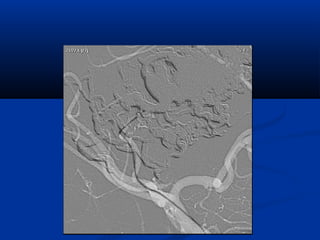

High flow characteristics

post traumatic AVM